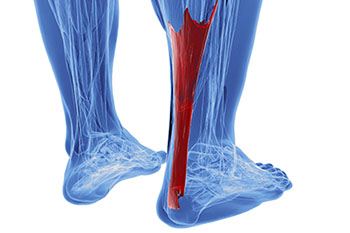

A condition that often results in serious heel pain is known as Achilles tendonitis. This condition may form when the Achilles tendon is damaged as a result of overuse. This particular injury can be very serious, as the Achilles tendon’s main function is to connect the lower half of the calf muscles to the heel bone. If this tendon becomes damaged, it may result in difficulty walking and completing everyday tasks, as well as cause extreme discomfort and pain.

It’s more common for athletes to experience Achilles tendon injuries, as they’re more likely to be participating in activities that would call for repetitive movement, such as running or jogging. This kind of repetitive movement over time is likely to cause stress on the tendon. When athletes abruptly increase their performance level without properly training or warming up their bodies, they may also injure the Achilles tendon, which may lead to inflexibility in the calf muscles.